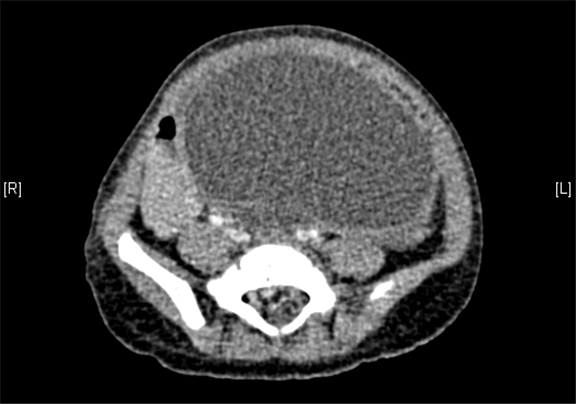

腹部三维动态CT:腹腔巨大囊性占位性病变,考虑肠系膜来源良性病变可能性大,腹腔肠系膜淋巴管瘤?

术前CT检查:

平衡期